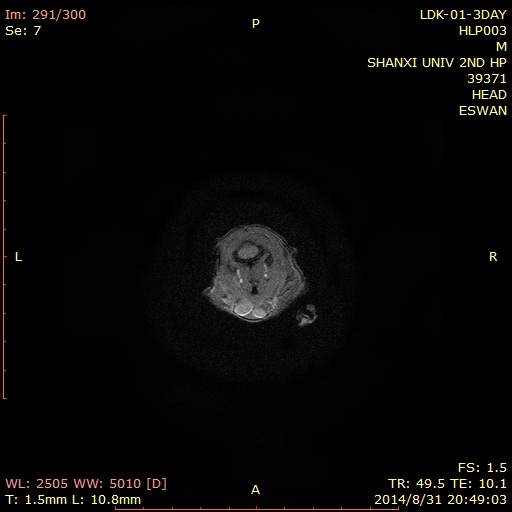

Matlab 7.0怎么处理swan图像得到幅度信号值、相位值。高人请进!